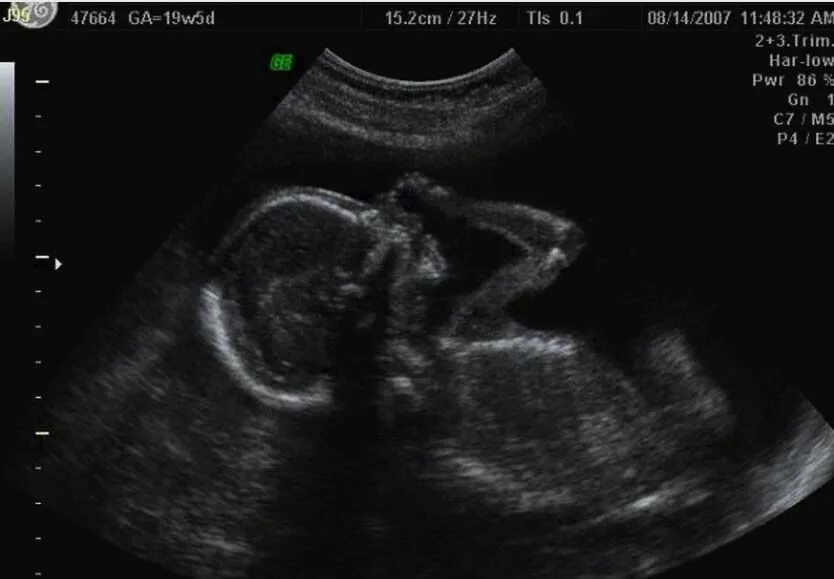

19 недель фото плода